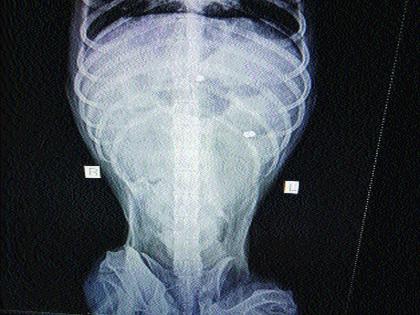

मुंबई : पवईतील एका उच्चभ्रू इमारतीत एअर गनने श्वानाला ठार मारण्यात आल्याची धक्कादायक घटना बुधवारी उघडकीस आली आहे. श्वानाच्या एक्सरेमध्ये एअर गनच्या दोन पॅलेट्स मिळाल्या आहेत. त्यानुसार, पवई पोलिसांनी अनोळखी व्यक्तीविरुद्ध गुन्हा दाखल करत अधिक तपास सुरू केला आहे.

५ डिसेंबर रोजी ब्राऊनी जास्तच अशक्त दिसू लागला. त्याने खाणे-पिणे बंद केले. तरीही त्याला कसेबसे जेवण भरविण्याचे प्रयत्न सुरू होते. पुढील औषधोपचारांसाठी खारच्या योडा अॅनिमल एनजीओ शेल्टर येथे नेण्यात आले. तेथून त्याला अन्य व्हेटर्निटी स्पेशालिटी येथे पाठवून तेथील डॉक्टरांनी त्याच्यावर औषधोपचार केले. तेथे ब्राऊनीचा एक्सरे काढण्यात आला. त्यात त्याच्या शरीरामध्ये एअर गनच्या दोन पॅलेट्स दिसून आल्या.

ही बाब समजताच सर्वांना धक्काच बसला. त्याच दरम्यान उपचारादरम्यान ११ तारखेला ब्राऊनीचा मृत्यू झाला. कोणी तरी एअर गनने ब्राऊनीला ठार मारल्याचा संशय वर्तविण्यात येत आहे. याबाबत तक्रारदार व्यावसायिक महिलेने पोलिसांत धाव घेत तक्रार दिली. त्यानुसार, पोलिसांनी अनोळखी व्यक्तीविरुद्ध गुन्हा दाखल करत अधिक तपास सुरू केला आहे.त्यातही १ डिसेंबर रोजी सकाळी साडेआठच्या सुमारास त्याच परिसरात राहणाºया बलदेव बजाज यांच्या कारच्या काचा फोडल्याची घटना घडली. त्यामुळे या दोन्ही घटनांमध्ये एकाच व्यक्तीचा हात असल्याचा संशयही वर्तविण्यात येत आहे.